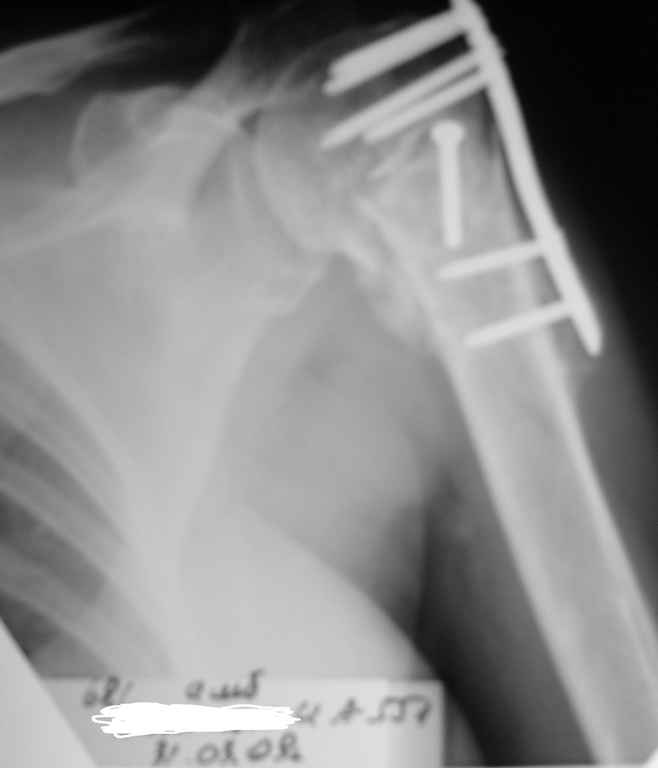

Пациентка Б.1953 г.р., врач-терапевт. Травма 27.11.08г. Падение с

высоты роста. Выявлен закрытый не осложненный оскольчатый перелом

хирургической шейки левого плеча со смещением.

02.12.08г. оперирована. Выполнена открытая репозиция и остеосинтез

пластиной LCP Деост с дополнительной фиксацией отдельно лежащего

фрагмента винтом. Послеоперационный период протекал без особенностей,

внутренняя ротация по 20 гр. На контрольных рентгенограммах

отмечается смещение металлоконструкции, ротация головки плеча с

приведением дистального отломка на 13 гр. и смещением к зади на 30 гр.

Рентгенограммы прилагаются. Ваш взгляд на дальнейшую тактику лечения

пациентки?